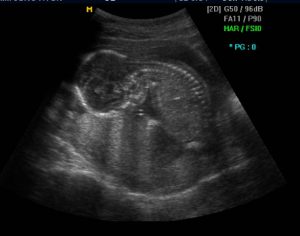

이번에도 또 엎드려서 고개를 있는대로 푹 숙이고 있는 모습에 그만 나는 털썩 했다.

교수님도 화면을 보시면서 애기가 편해서 그런건지,

아님 왜 저러고 있을까 하며 의아해 하셨고,

안되겠다 싶으신지 2주 뒤에 초음파를 보고 그때도 계속 이 자세이면

다른 검사를 해보자 하셨다.

그래도 이녀석 보기힘든 얼굴 겨우 봤더니~ 누구 닮았나~^^